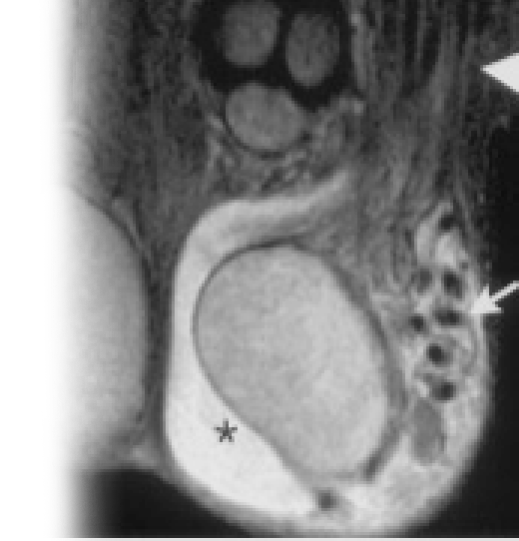

Магнитно-резонансная томография наружных половых органов – важный метод исследования, который позволяет визуализировать половые органы у мужчин и женщин.

Как проводится МРТ наружных половых органов?

Перед укладкой в томограф необходимо снять все металлические предметы. После этого пациент ложится на стол сканера, который постепенно перемещается в аппарат. Во время сканирования следует лежать неподвижно, чтобы получаемые изображения были четкими и неискаженными.